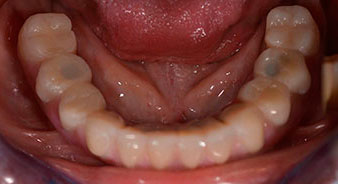

The 64-year-old patient presented with residual dentition of teeth 38, 33 and 43 and a clasp denture in the mandible (Fig. 1 and 2).

The impression and bite registration were then performed so that the dental technician could begin producing the provisional restoration immediately. This was then screwed in on the same day (Fig. 17 and 18).

Following the time required for the osseointegration, the final impression of the implants could be performed and the final denture produced accordingly (Fig. 19 and 20). At this point, the dentist and patient were able to decide together whether to use a ceramic or acrylic veneer and a zirconium or metal framework. In this case, Dr. Pascu’s team decided on an acrylic veneer based on the unclear prognosis for the maxillary dentition and the fact that tooth 24 is elongated. This type of veneer is generally considerably easier to adapt and can thus be subsequently altered to reflect the new situation in the maxilla.